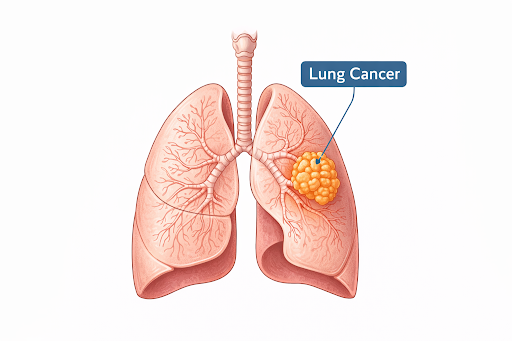

Overview

What is Lung Cancer?

Lung cancer is a type of cancer that begins in the lungs, the organs responsible for breathing. It occurs when abnormal cells in lung tissue grow uncontrollably and form tumours, which can interfere with normal lung function and may spread to other parts of the body.

Lung cancer is a type of cancer that begins in the lungs, the organs responsible for breathing. It occurs when abnormal cells in lung tissue grow uncontrollably and form tumours, which can interfere with normal lung function and may spread to other parts of the body.

How It Develops?

Lung cancer usually develops when normal lung cells undergo changes in their genetic material (DNA). These altered cells may begin to multiply uncontrollably, forming a tumour. Over time, cancer cells may invade nearby tissues or spread to distant organs.